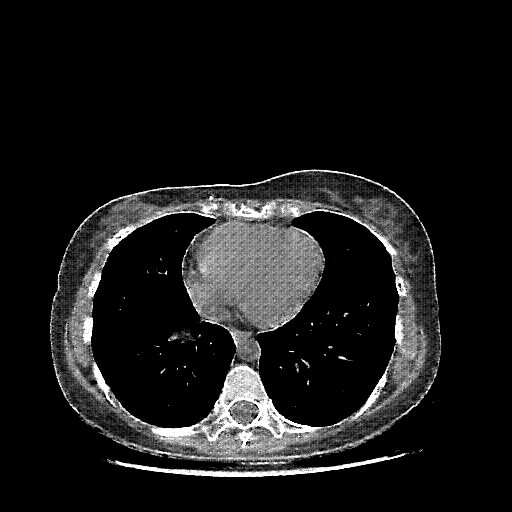

Targeted Slice 70 - Mediastinum Window Analysis (Generated vs Real Venous)

0.784

Mediastinum SSIM

43.0

Mediastinum RMSE

13.8

Mediastinum MAE

Average Mediastinum Window Metrics Across All Slices (103 slices) - Generated vs Real Venous

0.762

Mediastinum SSIM (Avg)

44.5

Mediastinum RMSE (Avg)

15.0

Mediastinum MAE (Avg)

Mediastinum window (WL 40, WW 400 β†’ Low βˆ’160, High +240)